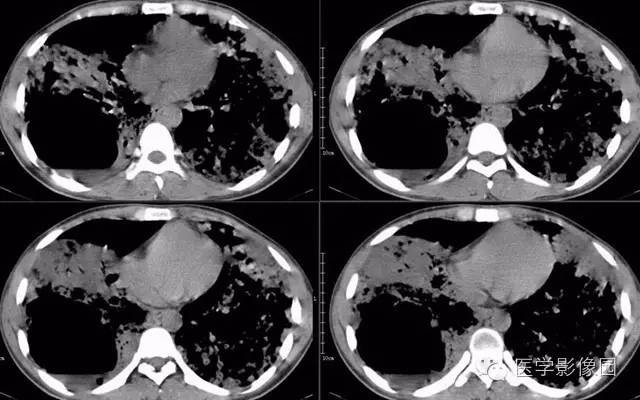

弥漫性肺泡细胞癌1例CT影像表现

病理结果:弥漫性肺泡细胞癌

弥漫性肺泡癌的主要临床及CT表现:临床表现无明显特征, 随着病情的进展, 咳嗽、 咳白痰、 进行性气促。CT表现 为病变分布有两种情况:病变累及一个肺段或肺叶;病变广泛分布于两肺。可归纳为5个特征性征象:蜂房征;支气管充气征;磨玻璃征;血管造影征;两肺弥漫分布的斑片状与结节影。